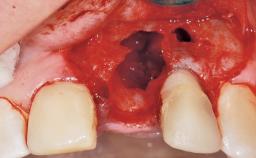

Late Flapless Placement of an Implant in a Maxillary Left Central Incisor Site

A 39-year-old male patient presented with a chief complaint of discomfort and gingival discoloration around his maxillary left central incisor. He was in good general health and was a non-smoker. His past dental history was significant because of the traumatic fracture of tooth 21 in a sporting accident at age 13. Initial dental treatment included endodontic therapy and a full-coverage restoration. The patient became symptomatic 5 years later, when structural failure of the tooth resulted in the dislodgment of the crown. Endodontic retreatment, apical surgery, and post-and-core restoration were performed.

Bone Augmentation Horizontal|Staged

Augmentation Materials Xenogenous|Membrane